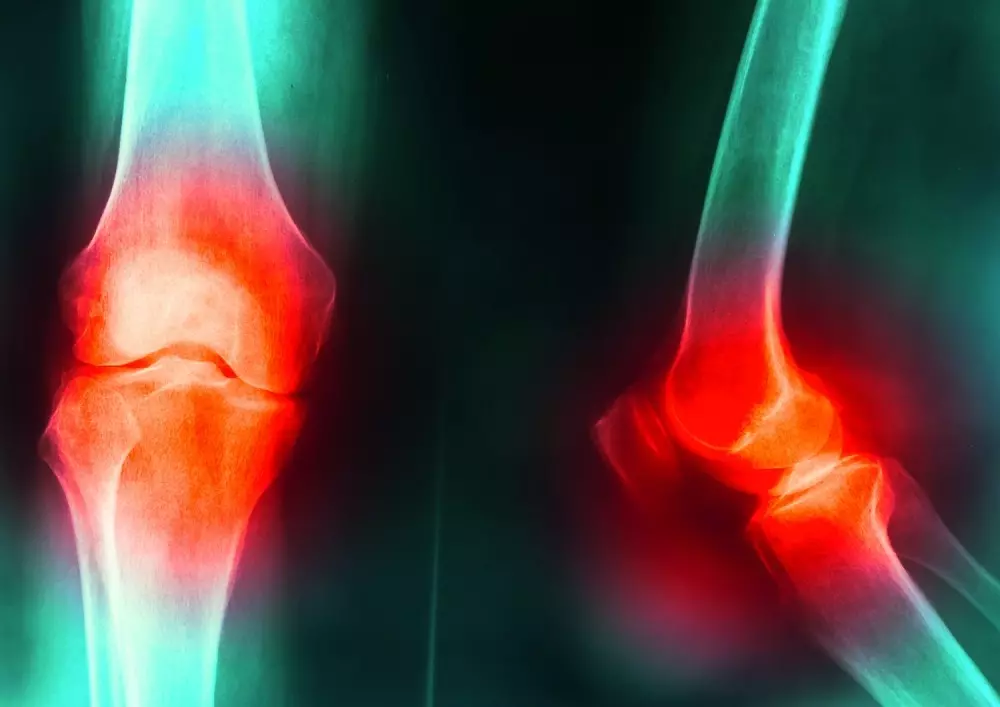

Kolano skoczka – metody lecznicze z punktu widzenia terapeuty

W dziale „Z praktyki gabinetu” znajdą Państwo tekst pt. „Kolano skoczka – metody lecznicze z punktu widzenia fizjoterapeuty”. Autor wskazuje na fakt, że zwiększona aktywność fizyczna, którą można zauważyć w ostatnich latach, sprzyja kontuzjom, przy czym szczególnie podatny jest na nie staw kolanowy o skomplikowanej budowie anatomicznej. Wśród tych kontuzji można wymienić właśnie kolano skoczka. „To uszkodzenie więzadła rzepki w miejscu, gdzie łączy się ono z rzepką. W tym newralgicznym miejscu sumują się różnego rodzaju mikrourazy, które w perspektywie czasu powodują degenerację tkanek” − pisze dr n. med. Kamil Klupiński.